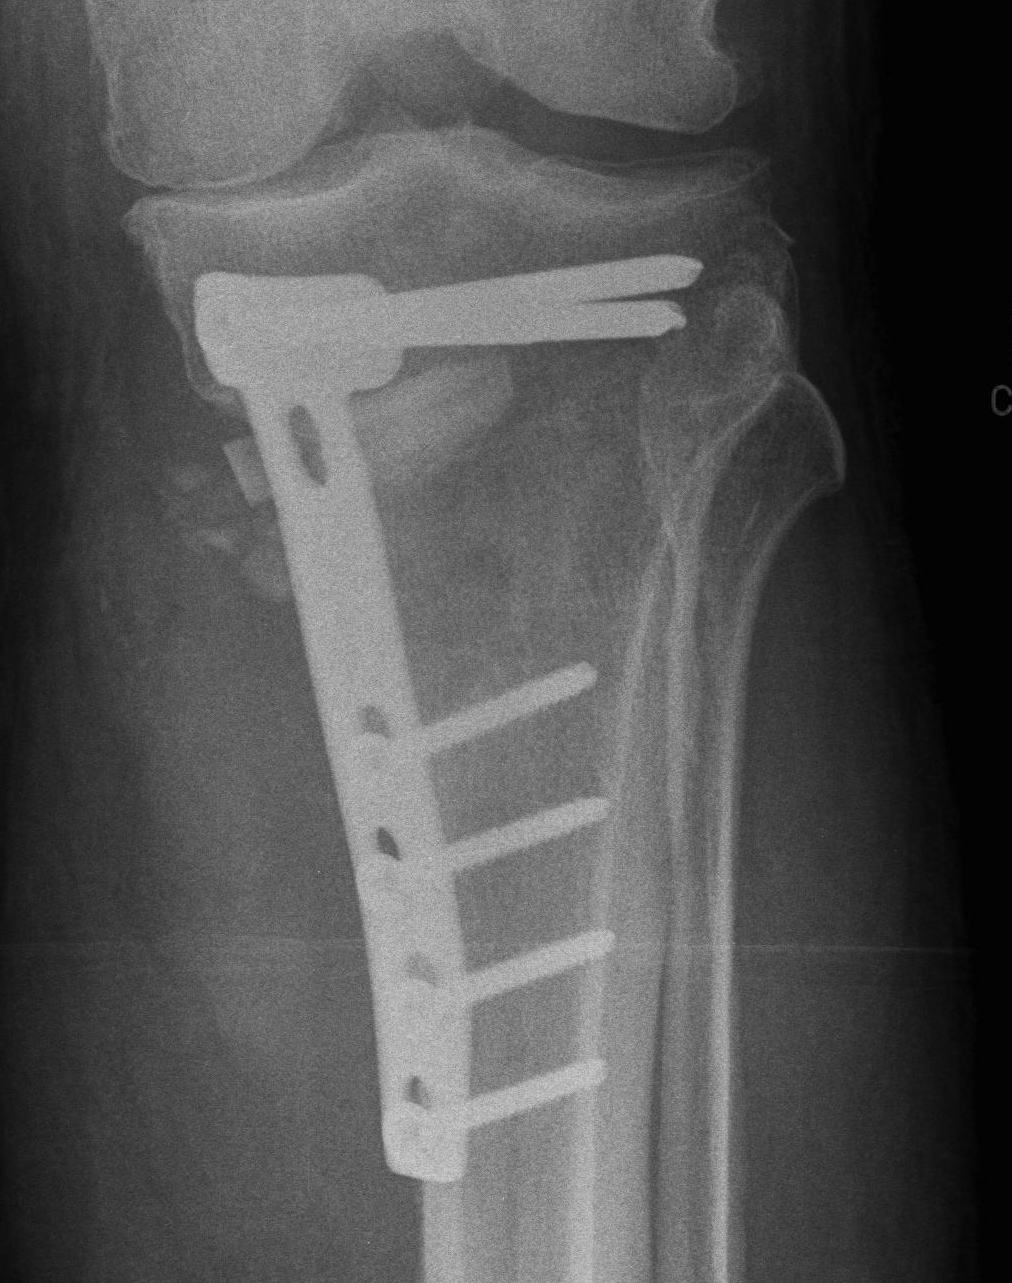

Stabilisation

- locking plates

- +/- autograft / allograft / synthetic bone graft

Arthrex Locking Puddhu plate PDF

Arthrex ContourLock system PDF